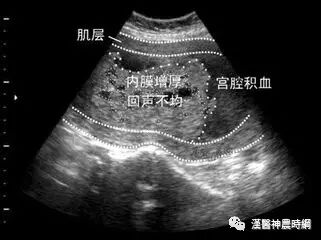

子宫内膜癌的主要症状

(一)子宫出血:绝经期前后的不规则阴道出血是子宫内膜癌的主要症状,常为少量至中等量出血,很少为大量出血。不仅较年轻或近绝经期患者易误认为月经不调,不及时就诊,即使医生亦往往疏忽。个别也有月经周期延迟者,但表现不规律。在绝经后患者多表现为持续或间断性阴道出血。子宫内膜癌患者一般无接触性出血。晚期出血中可杂有烂肉样组织。

(二)阴道排液:因腺癌生长于宫腔内,感染机会较宫颈癌少,故在初期可能仅有少量血性白带,但后斯发生感染、坏死,则有大量恶臭的脓血样液体排出。有时排液可夹杂癌组织的小碎片。倘若宫颈腔积脓,引起发烧、腹痛、白细胞增多。一般情况也迅速恶化。

(三)疼痛:由于癌肿及其出血与排液的瘀积,刺激子宫不规则收缩而引起阵发性疼痛,约占10~46%。这种症状多半发生在晚期。如癌组织穿透浆膜或侵蚀宫旁结缔组织、膀胱、直或压迫其他组织也可引起疼痛,往往呈顽固性和进行性加重;且多从腰骶部、下腹向大腿及膝放射。